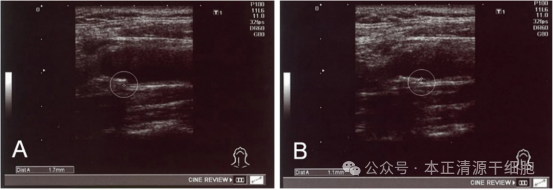

MSC 治疗前 ( a ) 和治疗后 ( b ) 的颈总动脉 IMT 示例显示,治疗后近 4 个月,IMT 从 1.7 毫米下降至 1.1 毫米

56岁的日本患者山田先生(化名)曾因1.7mm颈动脉斑块被心内科专家评估为 “极高危”。接受2亿个间充质干细胞静脉回输后,4个月后超声复查显示:

颈总动脉内膜中层厚度(IMT)从 1.7mm 降至 1.1mm,直接脱离 “颈动脉狭窄” 范畴。